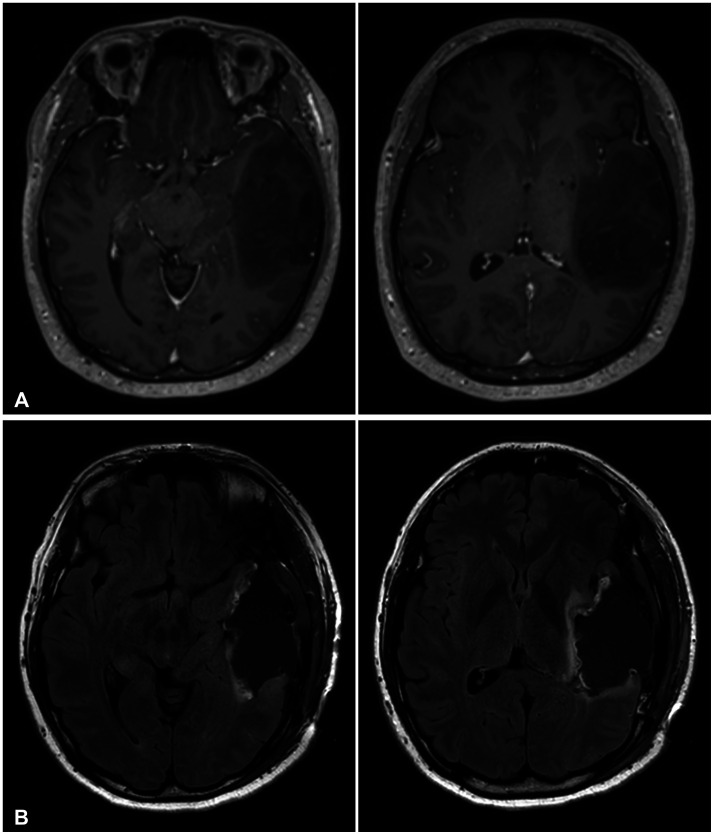

High-grade transformation of low-grade gliomas has long been a poor prognostic factor during therapy. In 2016, the World Health Organization (WHO) Classification of Tumors of the Central Nervous System (CNS) adopted isocitrate dehydrogenase (IDH) mutation status in the classification of diffuse astrocytomas. The 2021 classification denoted glioblastomas as IDH-wildtype and graded IDH-mutant astrocytomas as 2, 3, or 4. Gemistocytic morphology, a large proportion of residual tumor, the patient's age, and recurrence after radiotherapy were previously mentioned as risk factors for high-grade transformation of low-grade gliomas. We report a 34-year-old male patient initially diagnosed with IDH-mutant grade 2 astrocytoma according to the 2021 WHO classification of CNS tumors. As the first surgical resection achieved gross total resection on postoperative MRI, no adjuvant therapy was given and regular follow-up was planned. On 1-year follow-up MRI, two new enhancing nodular lesions appeared at the ipsilateral brain parenchyma abutting the surgical resection cavity. Salvage craniotomy achieved gross total resection, and the pathologic diagnosis was IDH-mutant WHO grade 4 astrocytoma. We describe this tumor in terms of the previous WHO classification to evaluate the risk of high-grade transformation and discuss possible risk factors leading to high-grade transformation of low-grade astrocytoma.